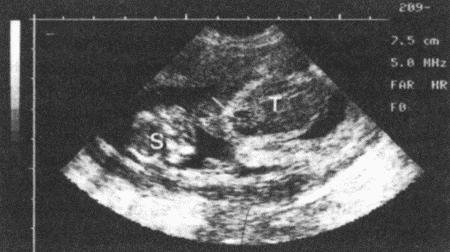

Содержание белков, таких, как фибриноген, в плазме крови во время так называемой протеиновой фазы повышается на 30–40 день беременности, причем данное явление не характерно для соответствующей стадии метэструса у небеременных сук. Повышение концентрации фибриногена в плазме измеряют с помощью иммунологических методов, а также с помощью существующего готового теста на беременность, хотя с распространением ультразвуковых методов необходимость в таком тесте постепенно снижается.